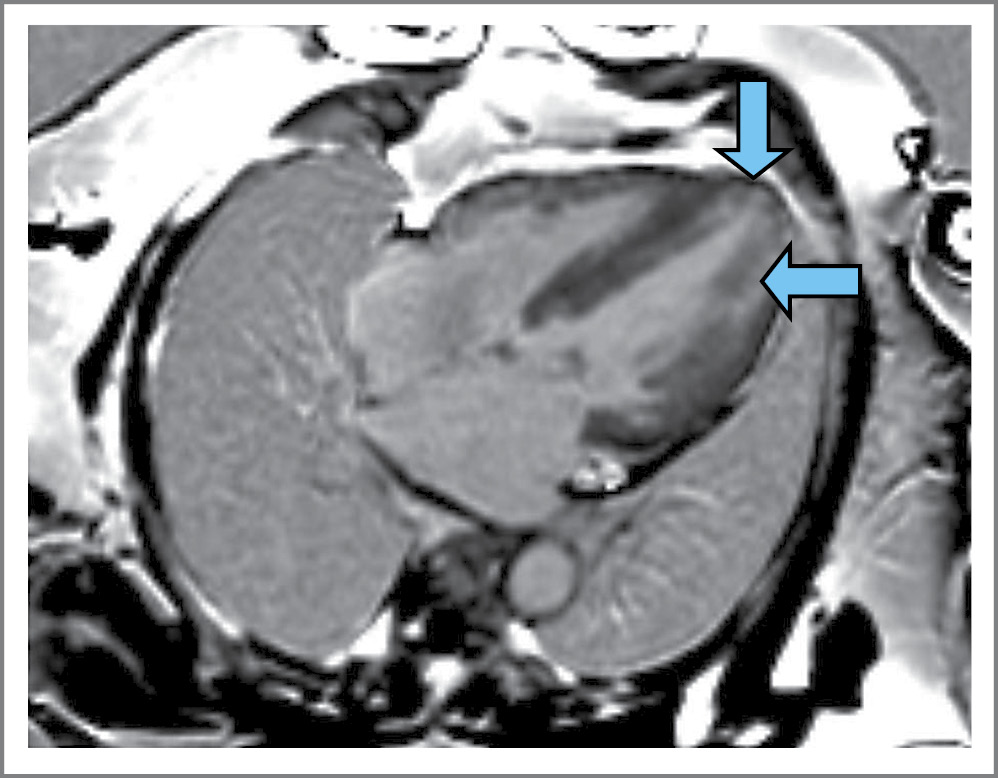

Выполнена коронароангиография от 15.11.2022: атеросклероз коронарных артерий без значимых стенозов. С 21.11.2022 в условиях кардиологического отделения №2 ГБУЗ ТО «ОКБ №1» инициирована ФЗТ. Все последующие инфузии ферментозаместительного препарата, вводимого через инфузомат и систему с фильтром, переносила удовлетворительно. Во время очередной госпитализации 13.10.2023 пациентка предъявила жалобы на прогрессирование одышки при физической активности, появление отеков лица в утренние часы. Холтеровское мониторирование электрокардиограммы (ЭКГ) от 16.10.2023: ритм синусовый 52–129–64 уд/мин, полиморфная желудочковая эктопическая активность в виде 2458 одиночных и 9 парных экстрасистол и неустойчивая желудочковая тахикардия с высокой частотой сердечных сокращений (2 эпизода) до 130 уд/мин и общей длительностью 6 с, 4 пробежки предсердной тахикардии, удлинение корригированного QT-интервала. МРТ сердца с внутривенным контрастированием от 21.10.2023: межжелудочковая перегородка (МЖП) – до 20 мм, боковая стенка – 27 мм. Толщина стенок правого желудочка (ПЖ) – до 9 мм. Поперечный размер ПЖ в диастолу – 79×32 мм. Продольный размер ПЖ – 63 мм. Фракция выброса (ФВ) – 64%, масса миокарда ЛЖ – 235 г. На постконтрастных изображениях участков замедленного вымывания контрастного вещества (КВ) не выявлено. Заключение: МР-картина симметричной гипертрофии миокарда ЛЖ; стеноз аортального клапана; средняя степень аортальной регургитации; эктазия ствола легочной артерии (ЛА), расширение ветвей ЛА; интрамиокардиального фиброза на момент исследования не получено. Пациентка консультирована сердечно-сосудистым хирургом, документы направлены в ФГБУ «НМИЦ им. акад. Е.Н. Мешалкина» для определения дальнейшей тактики ведения и лечения. Получен ответ 24.10.2023: показания к операции миоэктомии пути оттока ЛЖ сомнительны, продолжить специфическую терапию заболевания. Получены результаты из ФГБНУ «МГНЦ им. акад. Н.П. Бочкова» 26.10.2023: Lyso-Gb3 повышена – 5,04 нг/мл (норма – 0,05–3 нг/мл); 18.04.2024 впервые зафиксирован PQ/PR менее 120 мс (рис. 1). МРТ сердца с внутривенным контрастированием от 19.05.2024: МЖП – до 20 мм, боковая стенка – 10–12 мм. Конечно-диастолический размер ЛЖ – 45 мм, конечно-систолический размер ЛЖ – 26 мм, продольный размер ЛЖ – 97 мм. Толщина стенок ПЖ – до 4–5 мм, ФВ – 74%, масса миокарда ЛЖ – 287 г. На постконтрастных изображениях определяются интрамиокардиальные участки замедленного вымывания КВ по боковой стенке ЛЖ на уровне среднего и апикального сегмента, МЖП апикально соответствует зонам фиброзных изменений. Заключение: МР-картина асимметричной гипертрофии миокарда ЛЖ с признаками фиброзных изменений. Стеноз аортального клапана, аортальная регургитация 1-й степени. Эктазия ствола ЛА, расширение ветвей ЛА. В ФГБНУ «МГНЦ им. акад. Н.П. Бочкова» 30.07.2024 определена концентрация Lyso-Gb3 – 4,27 нг/мл (норма – 0,05–3 нг/мл). Динамика лабораторных исследований представлена в виде графиков (рис. 2, а, b). Данные эхокардиографии (ЭхоКГ) за 2 года наблюдения представлены в табл. 1.

В настоящее время для диагностики поражения сердца при БФ широко используется МРТ. ГЛЖ является наиболее распространенным структурным изменением, зарегистрированным при БФ. У пациентов преимущественно наблюдается концентрическая ГЛЖ с гипертрофией папиллярных мышц в начале, а асимметричная гипертрофия с грубо утолщенной перегородкой по сравнению с нижнебоковой стенкой развивается на поздних стадиях – заместительный фиброз вызывает истончение стенки последней. До 50% пациентов с БФ при МРТ будут иметь признаки контрастирования миокарда базального сегмента заднебоковой стенки ЛЖ в отсроченную фазу [5]. У нашей пациентки наблюдается замедленное вымывание контраста по боковой стенке ЛЖ на уровне среднего и апикального сегментов, МЖП апикально (рис. 4, 5, a, b). Также в случае нативного Т1-картирования при БФ отмечается значимое снижение глобального Т1-времени релаксации, что обусловлено накоплением гликосфинголипидов в кардиомиоцитах. При Т2-картировании повышение Т2-времени релаксации отмечается изолированно в заднебоковом сегменте ЛЖ, где чаще всего при БФ выявляется отсроченное накопление гадолинийсодержащего контрастного препарата. Повышение Т2 в данном сегменте объясняется очаговым отеком миокарда, а он, в свою очередь, связан с аномалиями на ЭКГ, которые могут провоцировать аритмии, включая измененный интервал PQ/PR, блокаду ножек пучка Гиса и удлинение интервала QTc. Данный отек и выброс высокочувствительного тропонина у пациентов с БФ связаны именно с локальным воспалением миокарда [6].

Рис. 4. МРТ сердца пациентки. Четырехкамерное сердце по длинной оси. Позднее усиление гадолиния отражает заместительный фиброз и помогает дифференцировать кардиомиопатию БФ от ишемической и других ГКМП. На постконтрастных изображениях стрелками показаны интрамиокардиальные участки замедленного вымывания КВ.

Fig. 4. Cardiac MRI of the patient. Four-chambered heart in long axis. Late gadolinium enhancement reflects substitution fibrosis and helps differentiate FD cardiomyopathy from ischemic and other hypertrophic cardiomyopathies. In post-contrast images, arrows indicate intramyocardial areas of delayed contrast washout.